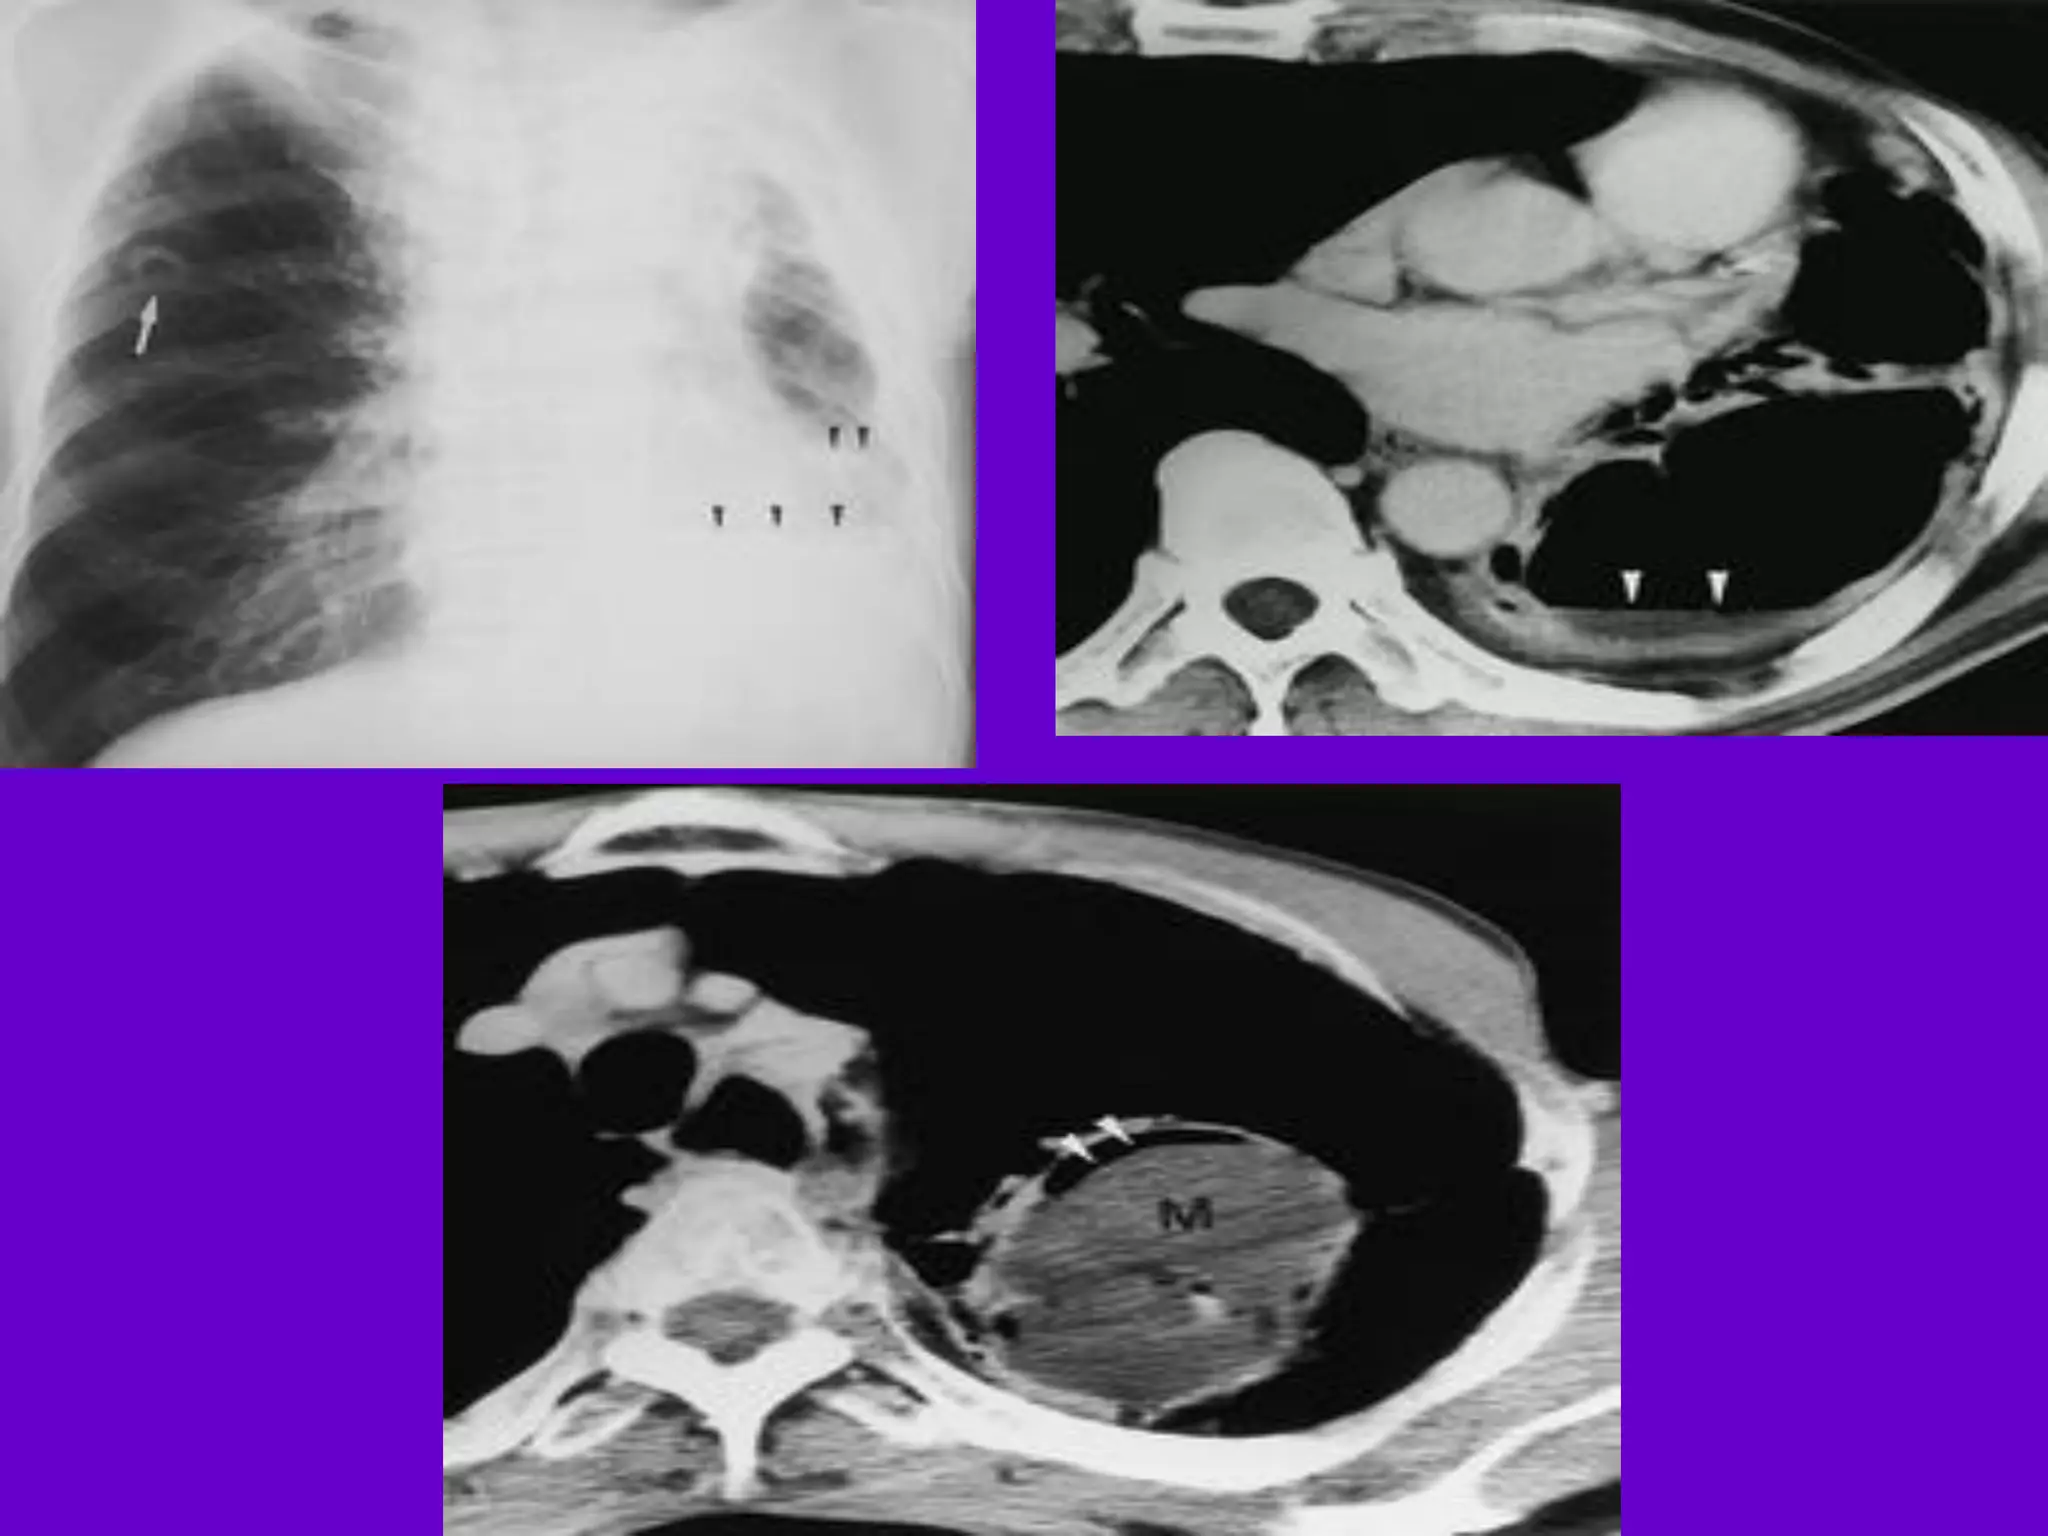

Pulmonary TB :

Lobar Pneumonia

􀂄

CT is superior than plain CXR in picking

up the

consolidation, atelectasis and the hilar LN

thereby

making the diagnosis easy.

􀂄 MRI reveals some of these changes,

however, CT is

the diagnostic modality of choice in such

cases.

Bronchopneumonia

On CT it is usually B/L and widespread,

not always

symmetrical involvement of lungs.

Hilar and Mediastinal

Lymphadenopathy

CT and MRI depict the hilar and

mediastinal LN

equally well.

􀂄 Calcification in the nodes is however

better seen on

CT.

􀂄 Necrosis is seen as focal areas of low

attenuation on

a CECT.

􀂄 On MRI focal necrosis is seen as areas

of increased

signal intensity on T2W images.

EBTB

HRCT is sensitive in the detection of

early

endobronchial spread of disease.

Miliary TB

􀂄 Earliest form of miliary TB is detectable

on HRCT.

􀂄 Coalescing nodules result into patchy

irregular

opacities and HRCT shows this variation

effectively

and has been described as “snowstorm

appearance”.

􀂄 HRCT shows cavitation, which is not

evident on plain

CXR.